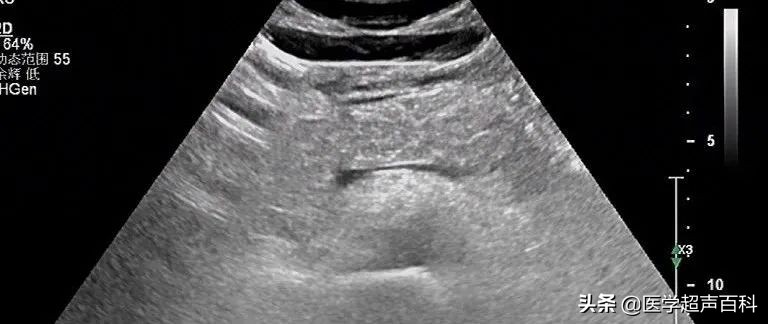

水肿型胰腺炎:胰腺稍大, 边缘规整,胰头、体部回声减低,分布前均质

急性胰腺炎声像图表现

(1)胰腺弥漫性或局限性增大,可失去正常形态,轮廓不清。

(2)内回声减低,呈弥漫分布的弱点状,中间有强弱不均、形态不整、边界不清的片状回声。严重水肿时呈透声暗区,似囊肿声像图。

(3)多伴胰腺区胃肠气体增多,以胰头区更甚,使探查更为困难。